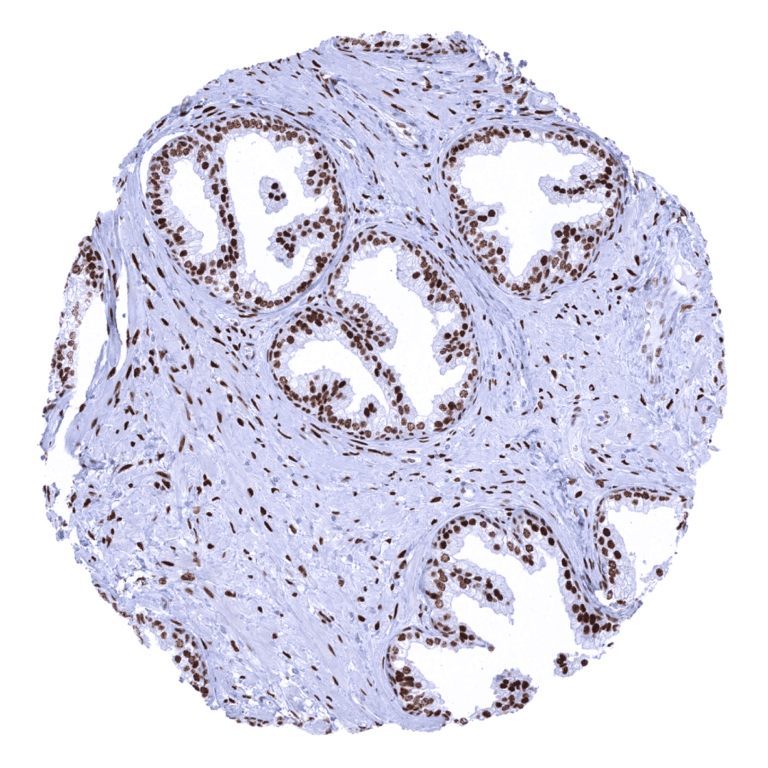

Androgen receptor immunostaining most prominently occurs in organs of the male genital system. In the prostate, seminal vesicle, and the epididymis, luminal, basal, and stroma cells stains strongly. In the testis, Sertoli, Leydig and stromal cells are AR positive. A moderate to strong staining is also seen in sebaceous glands and in several tissues of the female genital system. Here, a stromal and epithelial cell staining occurs in the myometrium, endometrium (stroma>epithelium), and endocervix of the uterus, the fallopian tube (stromal cells and intercalated cells), and the ovary (follicular cells, theca cells, stromal cells). A moderate AR immunostaining is also seen in hepatocytes, basal cells of the respiratory epithelium, a fraction of tubuli (mostly distal) and podocytes of the kidney, breast glands, and skeletal muscle cells. In squamous epithelium and transitional epithelium of the anal mucosa, a weak to moderate staining of a fraction of cells occurs, predominantly in the lower half of the epithelium. AR is also detectable in the basal cell layers of tonsil crypt epithelium and in a fraction of thymic epithelial cells. A weak AR immunostaining also occurs (at least occasionally) in gallbladder epithelium, excretory and intercalated ducts of the pancreas, glandular cells of salivary glands, gastric glands, decidua cells, placenta trophoblastic cells (predominantly in the first trimenon), thyroid glandular cells, adenohypophysis (few cells with weak staining), urothelium, stroma of the glans penis, smooth muscle of kidney pelvis, and in a fraction of cells in the aortic wall. AR immunostaining is completely absent in the adrenal gland, corpus luteum of the ovary, hematopoietic and lymphoid tissues, many mesenchymal tissues, surface epithelium of the gastrointestinal tract, lung, neurohypophysis, and the brain.

A total of 14,408 tumors from 141 different tumor categories were successfully analyzed by using the following protocol: Heat-induced antigen retrieval for 5 minutes in an autoclave at 121°C in pH 7,8 Target Retrieval Solution buffer. MSVA-367R, at a dilution of 1:150 at 37°C for 60 minutes. Visualization of bound antibody by the EnVision Kit (Dako, Agilent). This protocol was also used for all stainings depicted in our tumor and normal tissue galleries.

Freshly cut sections should be used (less than 10 days between cutting and staining). Heat-induced antigen retrieval for 5 minutes in an autoclave at 121°C in pH 7,8 Target Retrieval Solution buffer. Apply MSVA-367R at a dilution of 1:150 at 37°C for 60 minutes. Visualization of bound antibody by the EnVision Kit (Dako, Agilent) according to the manufacturer’s directions.